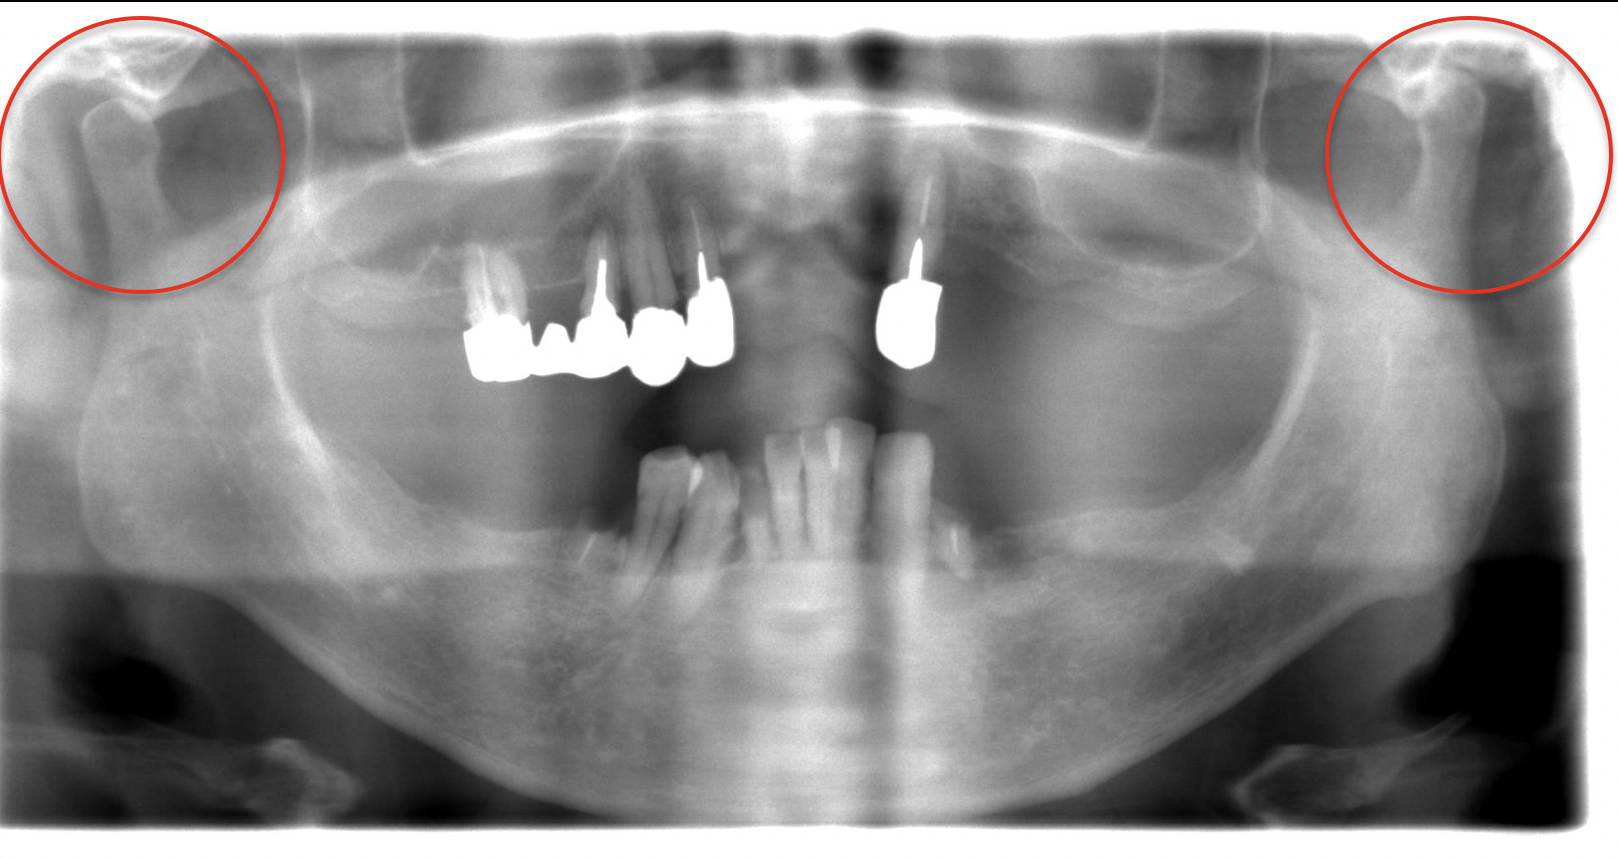

初診時パノラマ

下顎臼歯部の顎堤は吸収が少なく、十分な高さがありますが、その一方、上顎の欠損部顎堤は大きな骨吸収が認められます。

また、左右の下顎頭は、その位置に左右差が認められます。その運動が連動しておらず、左側において運動が阻害されていることが考えられます。ただし、視診・触診より開口障害や疼痛、関節雑音は認められませんでした。